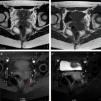

Imágenes axiales potenciadas en T1 y T2 (1, 2). Imágenes potenciadas en secuencias T1 Fat-SAT pre y posgadolinio (3, 4). Las imágenes potenciadas en T2 muestran en el suelo pélvico una lesión espiculada e hipointensa (flechas blancas) dentro del muro pélvico izquierdo, localizada en la entrada del nervio pudendo en el canal de Alcock. La lesión (flechas blancas) muestran una señal de mediana intensidad en imágenes potenciadas en T1 y secuencias T1 Fat-SAT, con un foco de hiperintensidad (flecha roja en 3), relacionada con restos de sangrado. Después de la administración de gadolinio la lesión capta de forma heterogénea (4).La figura en color está disponible en la versión on-line.

Presentamos el caso de una mujer de 30 años de edad, sin antecedentes clínicos, ginecológicos o traumáticos relevantes, que inicia dolor espontáneo recurrente localizado en la región perineal y glútea interna del lado izquierdo. La paciente describe el dolor como una sensación de punzadas dolorosas, hormigueo y quemazón, junto con hipersensibilidad localizada que se agrava al tacto de la zona o al sentarse, mejorando al levantarse o tumbarse. La paciente no manifiesta en ningún momento disfunción esfinteriana ni incontinencia, tanto vesical, como anal. El dolor es intenso siempre con el mismo recorrido y distribución anatómica. El dolor persiste durante varios días de forma fluctuante, pero puntualmente siempre reaparece hacia la mitad del ciclo menstrual y con la aparición de la menstruación. En la exploración física que se realiza sobre la zona génito-perineal la paciente describe dolor intenso durante la realización del tacto rectal, que aumenta con la movilización del cuello uterino. En el tacto vaginal se aprecia la presencia de un cordón fibroso muy doloroso a la palpación, localizado en la espina ciática izquierda y que no se detecta en la palpación de la zona contralateral. En la exploración cutánea perineal izquierda la paciente presenta un signo de Tinel positivo acompañado de hiperalgesia cutánea de la zona, sin una clara hipoestesia localizada acompañante, pero con reflejos anal y bulbocavernoso conservados. Ante los síntomas clínicos descritos en la anamnesis y los hallazgos clínicos detectados en la exploración se realizan pruebas de imagen complementarias para detectar la presencia de lesiones de perfil endometrial como causantes de la sintomatología que describe la paciente. En la evaluación ecográfica ginecológica no se detectan alteraciones estructurales significativas. La paciente reusó la posibilidad de realizar estudio neurofisiológico de la zona afectada por el dolor. No obstante y ante la persistencia clínica de la sintomatología se realiza durante el período menstrual de la paciente una resonancia magnética de la región pélvica con y sin contraste, que logra detectar la presencia de una lesión hemorrágica en la región inferior del muro pélvico, a nivel de la entrada del nervio pudendo izquierdo en el canal de Alcock, compatible con endometriosis (fig. 1).